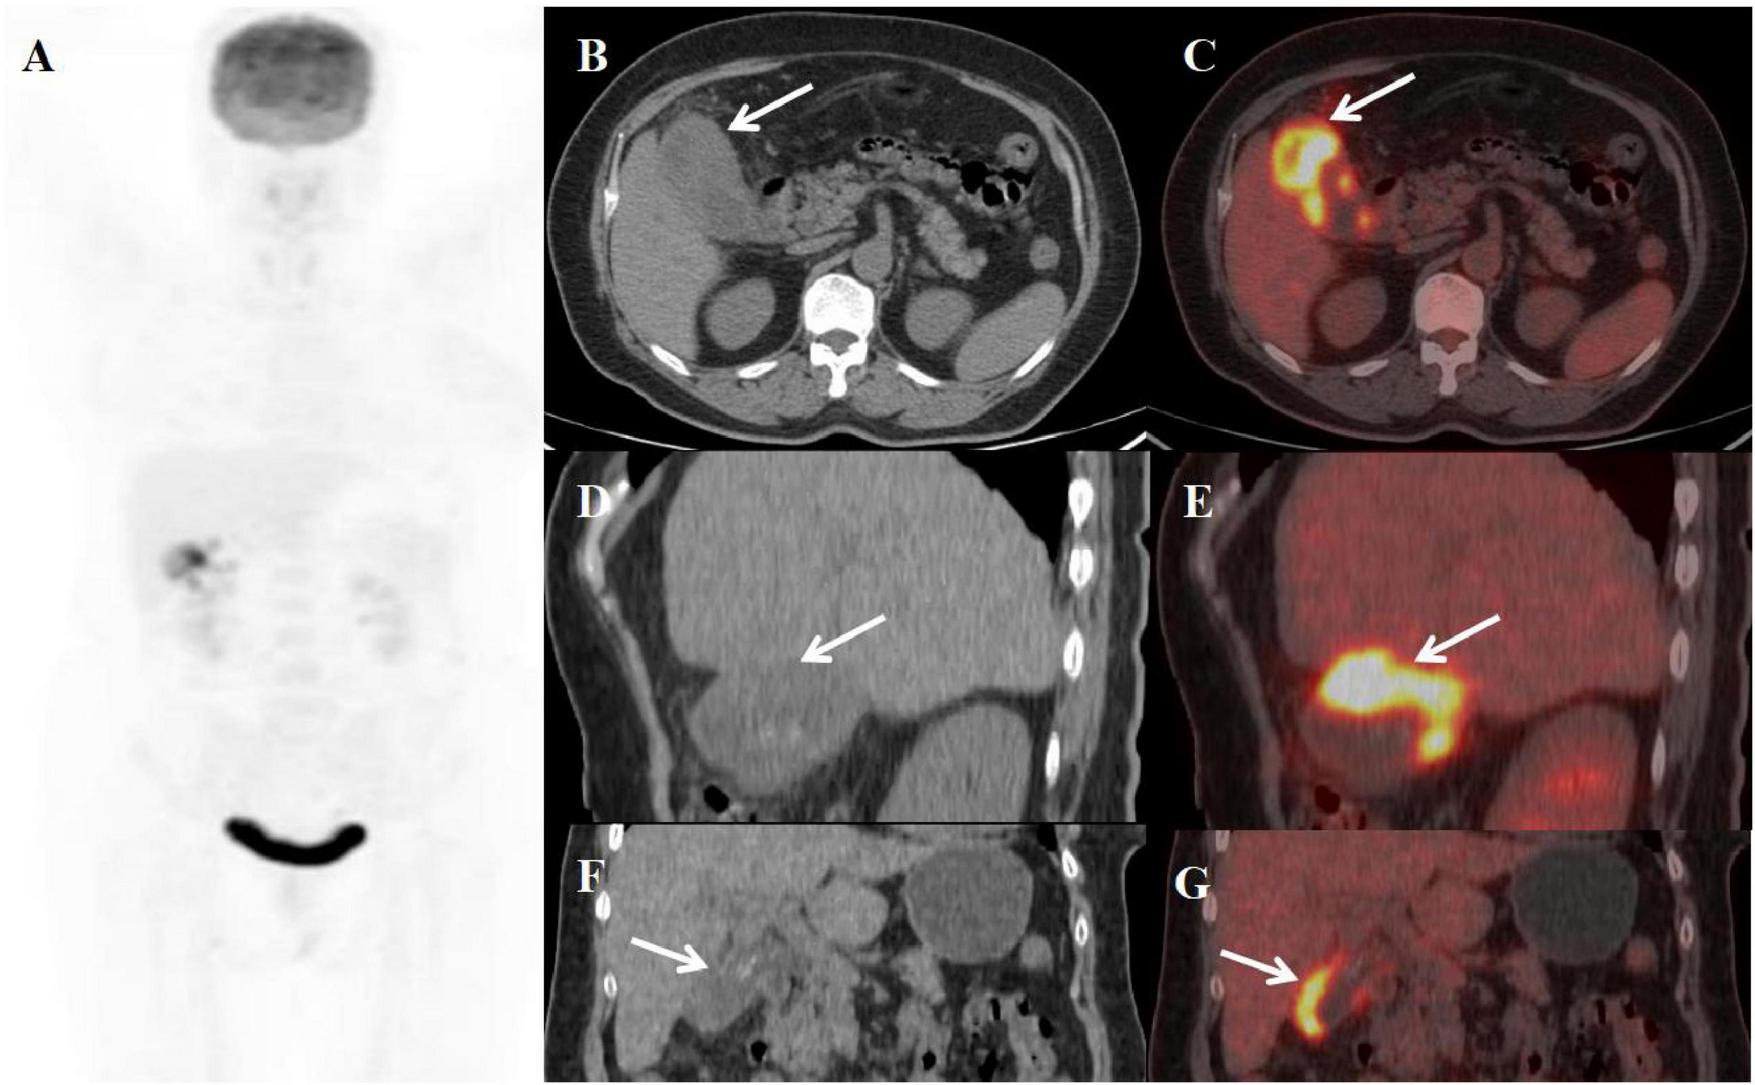

An 84-year-old woman presented with a two-day history of abdominal pain. Physical examination revealed a positive Murphy’s sign. Laboratory evaluation revealed leukocytosis (WBC count: 11.43 × 109/L) with neutrophil predominance (85%). CRP was elevated (15 mg/L). All tumor markers were within normal limits. Since the possibility of malignant gallbladder lesions could not be excluded, the patient underwent PET/CT in our department. The imaging revealed a constricted gallbladder lumen with diffuse wall thickening, measuring up to 1.9 cm at its maximum. The mucosal line remained intact. The liver-gallbladder interface appeared blurred, with a round, mildly hypodense lesion (approximately 2.3 cm in diameter) observed in the adjacent hepatic parenchyma. Furthermore, the thickened gallbladder wall demonstrated adhesion to the duodenal bulb. These lesions exhibited increased FDG avidity, with a SUVmax of 6.5 (Figure 5). Concurrent gallbladder stones were also identified. The patient subsequently underwent cholecystectomy with partial resection of liver segment V and adhesiolysis. Postoperative histopathological examination confirmed the diagnosis of XGC with concurrent hepatic abscess.

Figure 5. Female, 84 years old. (A) (whole body MIP), (B, C) (Axial CT and fused axial PET-CT), (D) (Fused coronal PET-CT), and (E) (Fused sagittal PET-CT). 18F-FDG PET/CT Imaging Findings: The gallbladder demonstrates diffuse wall thickening (maximum 1.9 cm) with luminal narrowing (A, arrow ↑), while maintaining mucosal integrity. The hepatobiliary interface appears indistinct, with a 2.3 cm mildly hypodense hepatic lesion noted adjacent to the gallbladder (B, arrow ▲). The thickened gallbladder wall shows duodenal bulb adhesion, with both the mural thickening and adjacent hepatic lesion exhibiting moderate FDG avidity (SUVmax 6.5). Associated cholelithiasis is present.